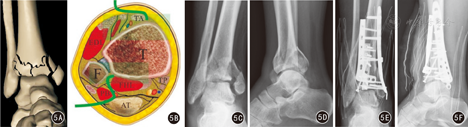

垂直压缩型Pilon骨折9例均采用前内、后外侧联合入路。根据踝关节水平面CT中的骨折线,参照Tornetta[3]的方法测量骨折角。根据各骨折块的解剖关系和骨折线的走行,选择手术入路和固定方式。(1)骨折角>90°、骨折线呈冠状面走行、压缩骨块偏内侧者,采用前内侧入路联合后外侧入路,通过上述两个切口同时显露胫骨远端的内、前、外、后侧及距骨关节面,将支撑钢板放置在胫骨前内和后外侧垂直骨折线固定骨折。(2)骨折角<90°,骨折线呈矢状面走行等,根据Topliss骨折分型方法[6],标出主要骨折线的位置,把矢状面Pilon骨折分为单纯矢状面劈裂、"T"形和倒"V"形压缩骨块3型。根据骨块及骨折线的位置多采用后外侧入路联合前内侧入路。首先纠正胫骨干骺端短缩畸形,牵引踝关节,通过软组织铰链作用恢复踝关节前、后、前外侧、后外侧和内踝等周围有韧带关节囊附着的骨块。前内侧入路暴露内侧和前外侧骨块间的骨折线,开窗撬拨、暴露中央压缩骨块,以距骨关节面为模板复位压缩的踝关节面并植骨填充骨缺损,克氏针临时固定,关窗,X线透视踝关节机械轴线和关节面复位情况,分别用支撑钢板固定踝关节周围较大骨块(图5)。内固定材料有克氏针、空心钉、解剖型锁定接骨板、T型或1/3管型接骨板、跨关节外固定支架等。

垂直压缩型Pilon骨折,胫骨关节面多个粉碎压缩骨块,但有分布规律,需联合入路进行骨折的暴露、复位和固定,前内侧入路联合后外侧入路是经典的联合切口。传统的前内侧入路为沿胫骨嵴内侧由近向远纵行切开,在踝关节线近侧2.5 cm处弧向内侧至内踝前方。该切口能处理绝大多数的胫骨内侧和正中关节面的Pilon骨折,但暴露外侧的Chaput骨折块时常比较困难,而且过度牵拉和剥离软组织会导致更高的皮瓣坏死率和伤口感染率。改良的前内侧入路较传统前内侧入路稍偏外,可同时显露胫骨内侧、正中和部分外侧关节面,利于术中复位和固定骨块,减少对切口皮肤的牵拉。对于传统前后联合入路,通常认为两个切口间的皮桥宽度应大于7 cm[15]。垂直压缩型Pilon骨折的胫骨关节面和干骺端常为粉碎性骨折,关节面出现塌陷、爆裂,术中复位困难,而该类型腓骨通常受损较轻,骨折复位相对简单、容易,且可确切恢复腓骨长度。牵引踝关节,通过踝关节周围韧带和关节囊牵引复位踝关节周围压缩骨块,纠正干骺端短缩畸形。后外侧入路复位固定腓骨和胫骨后外侧压缩骨块,前内侧入路开窗暴露中央压缩骨块,复位后克氏针临时固定,骨缺损处少量植骨以支撑中央压缩骨块,支撑接骨板分别固定胫骨远端内侧和前外侧压缩骨块。本组9例垂直压缩型Pilon骨折均采用后外侧入路联合前内侧入路,术后Burwell-Charnley放射学评价标准解剖复位2例、较好4例、一般3例。